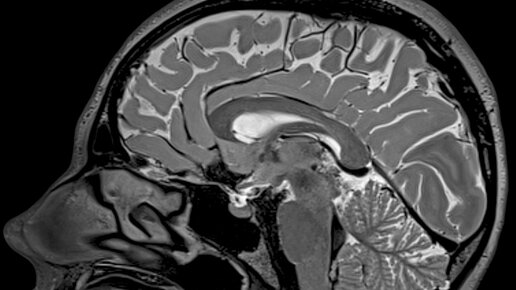

Чем отличается МРТ головного мозга от МРТ сосудов головного мозга? МРТ головного мозга и МРТ сосудов головного мозга - это два различных вида обследования.